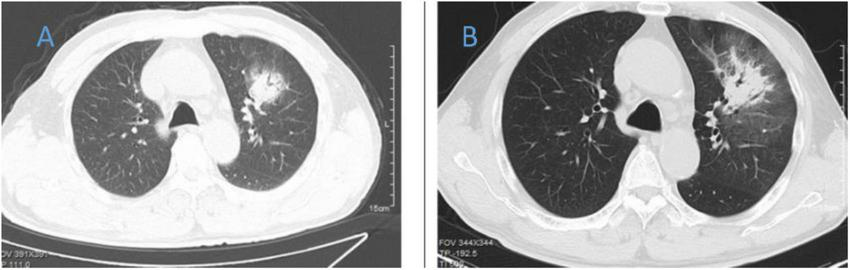

FIGURE 2

Chest CT of patient 2. (A) Before treatment on 2020.8.29; (B) the follow-up imaging 1 week after treatment showed progression compared to the pre-treatment scans.

FIGURE 3

Chest CT of patient 3. (A) Before treatment on 2021.12.11; (B) the follow-up imaging 1 week after treatment showed progression compared to the pre-treatment scans.